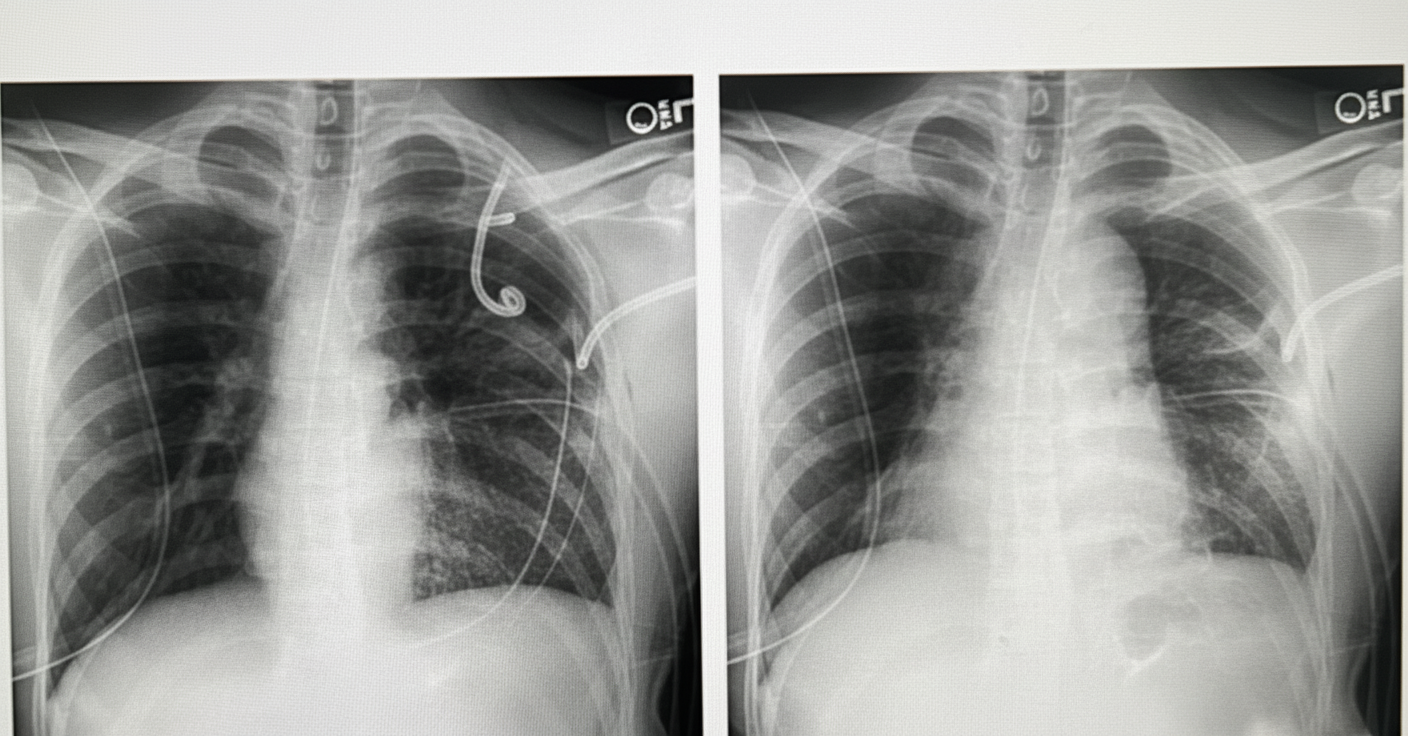

A 50-year-old patient presents to the ER with a history of a road traffic accident. The patient is unconscious. e-FAST revealed fluid in the pelvis. Chest X-ray is provided. What is the most likely diagnosis?

Explanation: ***Diaphragmatic rupture*** - High-velocity **blunt trauma** from road traffic accidents commonly causes diaphragmatic rupture, with **bowel or stomach herniation** into the chest cavity visible on chest X-ray. - The presence of **pelvic fluid on e-FAST** suggests multiple organ injury, consistent with severe blunt abdominal trauma that can rupture the diaphragm. *Pneumothorax* - Would present with **absent breath sounds** and **lung collapse** on chest X-ray, not bowel/stomach in the thoracic cavity. - **e-FAST pelvic fluid** is unrelated to pneumothorax and suggests intra-abdominal injury rather than isolated chest trauma. *Pulmonary embolism* - Typically occurs in patients with **risk factors** like prolonged immobilization, surgery, or malignancy, not immediately after acute trauma. - Chest X-ray would be **normal or show subtle changes**, not the dramatic findings of bowel/stomach in the chest. *Collapsed right lung* - Would show **complete opacification** of the right hemithorax with **mediastinal shift** away from the affected side. - Does not explain the **pelvic fluid on e-FAST** or the specific radiographic appearance of abdominal contents in the chest.